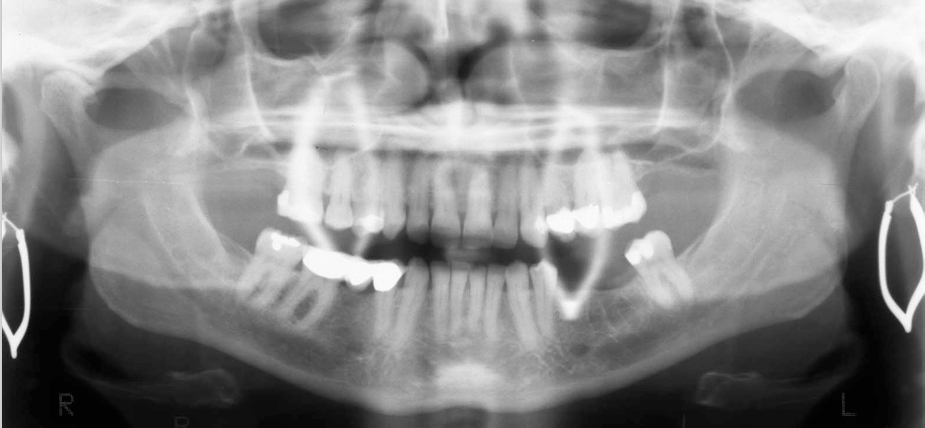

What is wrong with this image?

Inferior turbinates and meati spread across maxillary sinuses (too far back)

(also ghost image of earrings?-haley)